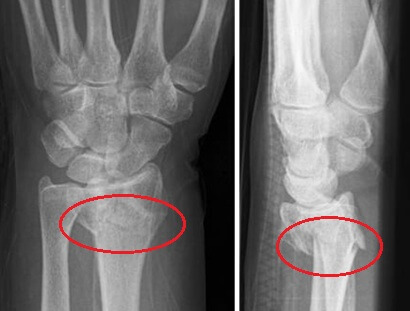

Broken Wrist Xray showing distal radius fracture

• X-rays: A broken wrist x-ray is the most common imaging method used to confirm a wrist fracture and determine its location and type